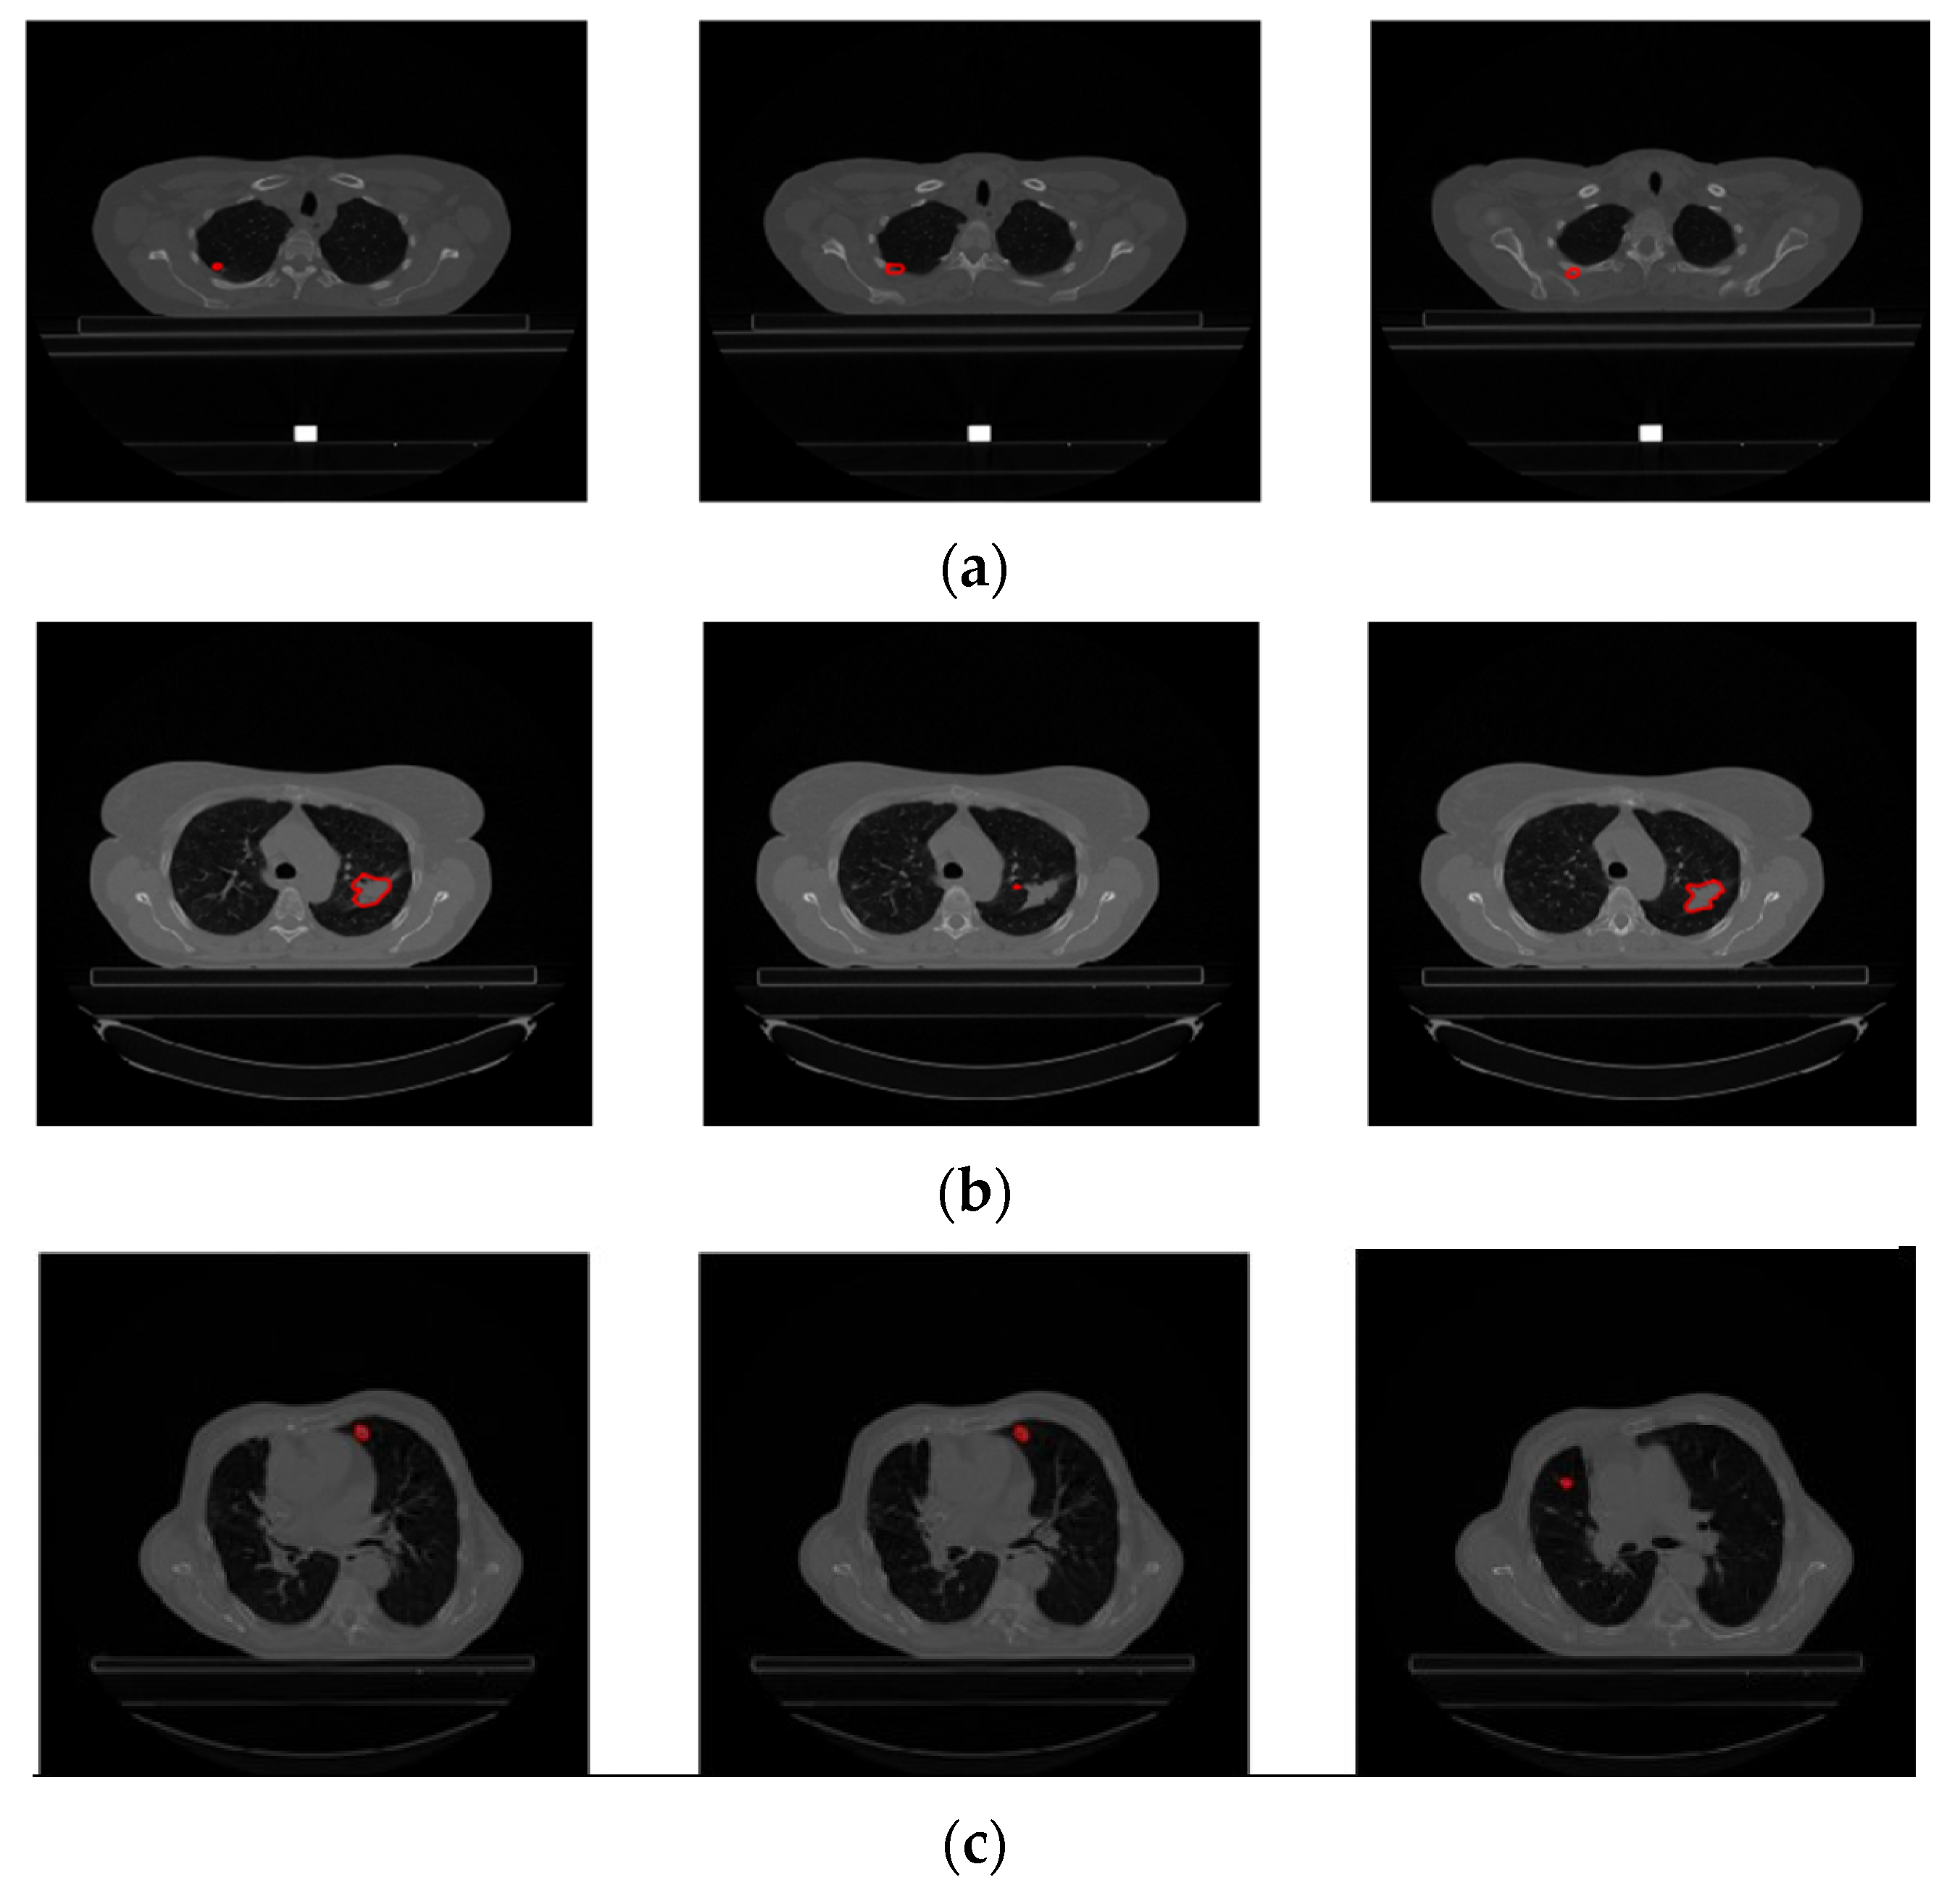

In the previous literature addressing similar problems to ours, only tumor regions from patients labeled as GTV-1 were utilized. The dataset contains a variable number of images with GTV-1 labeled tumors, ranging from 2 to 97. Figure 4 shows CT slices from a patient (LUNG1-243) with GTV-1 regions marked. There are 94 slices and 13 GTV-1 labeled tumor regions (Slice 21 through Slice 33) for this patient. For all patients in the dataset, Slice Thickness is given as 3.0 mm and Pixel Spacing is 0.977 mm.

Upon examination of Figure 4, it is evident that GTV-1 information is absent in each slice. As a result of a detailed analysis of the Lung1 dataset, Braghetto stated that 5 patients were incorrectly segmented due to incorrect labeling of tumor regions, 62 patients due to interpolation of segmentation images in consecutive slices, and 3 patients due to the presence of more than one tumor in one image [23]. The representation of each error type is given in Figure 5.

Figure 4. CT slices from patient LUNG1-243 and representation of tumor areas with GTV-1 labeling.

Figure 5. Incorrectly segmented images. (a) Incorrect labeling of tumor regions (LUNG1-158), (b) interpolation of segmentation images in consecutive slices (LUNG1-127), (c) presence of more than one tumor in an image (LUNG1-326).